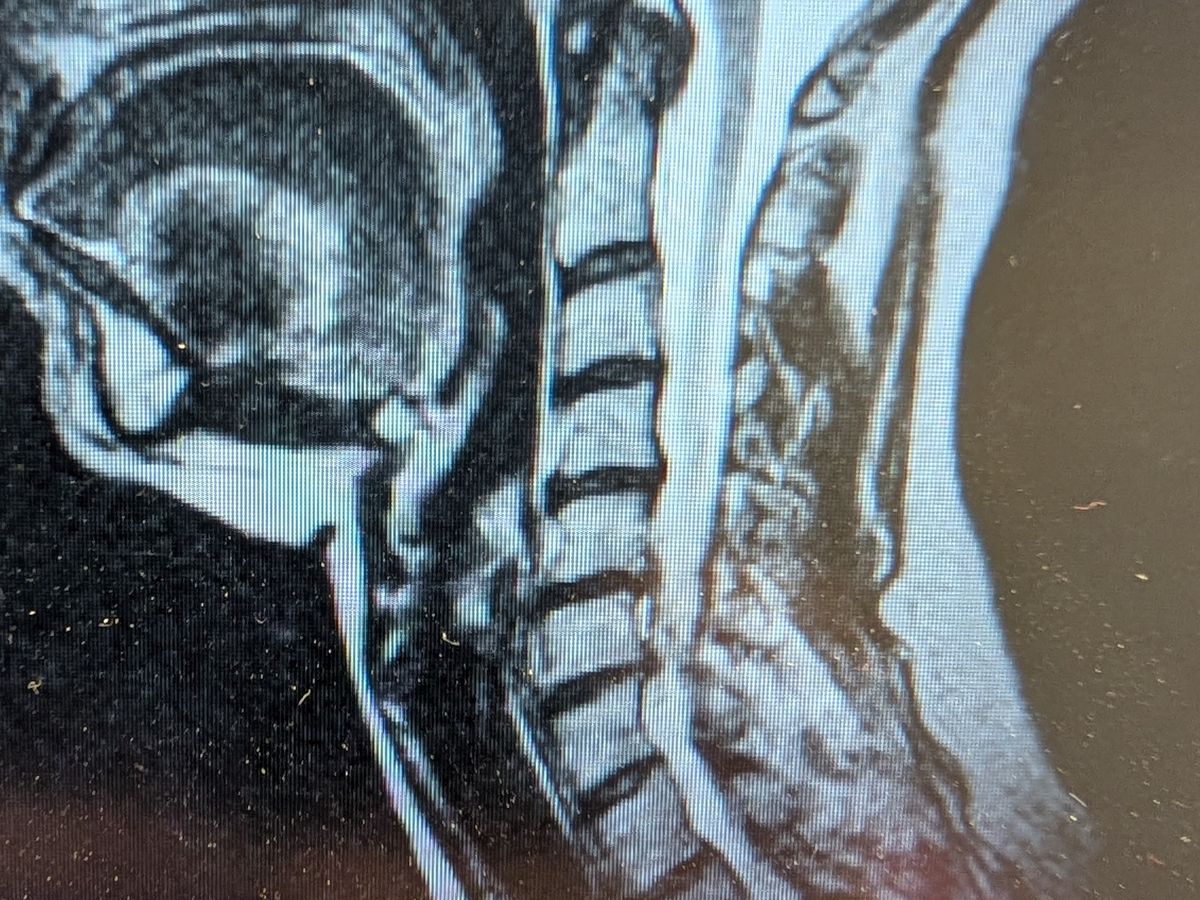

I am facing cervical spine surgery, and I'm raising funds to cover 6 weeks of living expenses! Insurance has my surgery covered, and I have less than 50 hours of PTO, but I need funds to cover the rest of my recovery time since I do not have short or long-term disability. Any and everything will help! Thank you, and God bless!